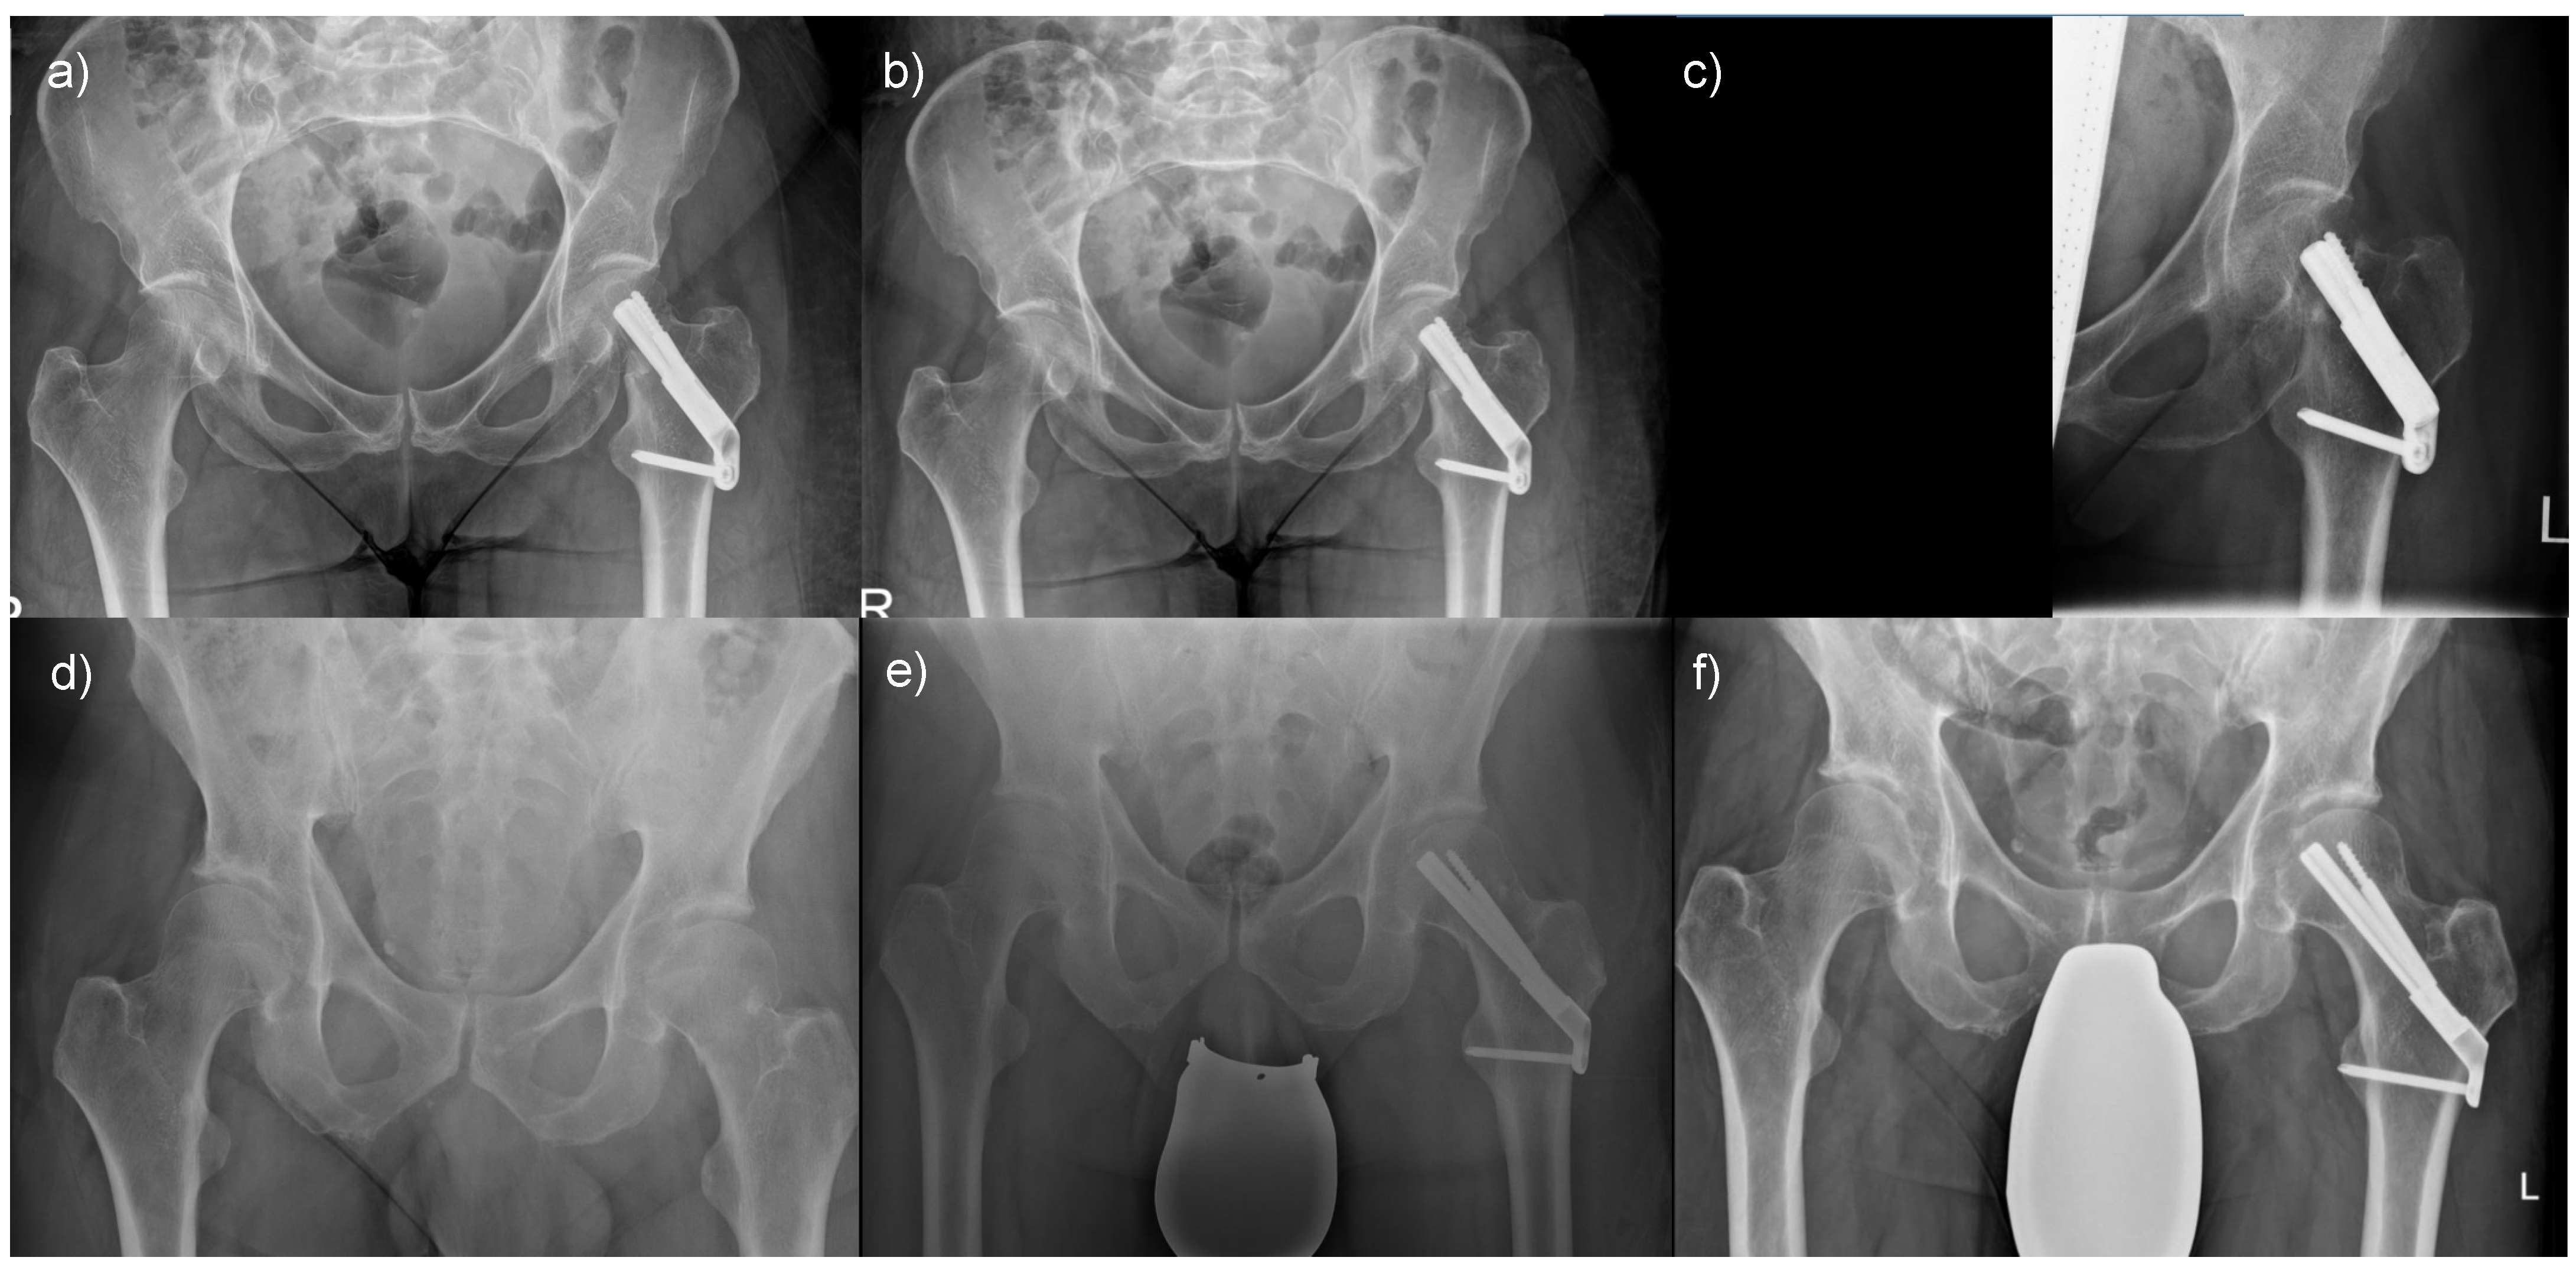

We assessed radiographic parameters in plain anterior–posterior radiographs of the pelvis using the MERLIN Diagnostic Workcenter (MERLIN Diagnostic Workcenter for Microsoft Windows, Version 5.8.1, Phönix-PACS GmbH, Freiburg im Breisgau, Germany). As previously described, Pauwels and centrum–collum–diaphyseal (CCD) angles were measured in the last preoperative and first postoperative radiographs [20]. Also, CCD angles, femoral offset, and leg length were evaluated using the earliest postoperative and follow-up radiographs at six months (Figure 1).

Figure 1.

Plain anterior–posterior radiographs of the pelvis visualizing leg length and femoral offset measurements. Two parallel bisections of the femoral shaft (a, b) determined the longitudinal femoral shaft axis (c). Perpendicular to (c), the leg length (d) was measured between the femoral head centre (e) and the tip of the lesser trochanter (f). The femoral offset (g) was measured between the femoral head center (h) perpendicular to (c).

As depicted in Figure 1, radiographic assessments were conducted in a standardized fashion using MERLIN Diagnostic Workcenter. Figure 3 provides an illustrative representation of the respective measurements for femoral offset, the CCD angle, and the radiographic leg length associated with each incorporated implant. The outcomes of each evaluation were directly annotated by the software within the radiograph.